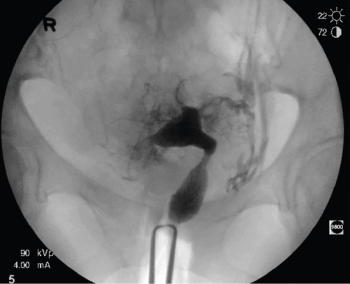

Discover how FemaSeed, an innovative artificial insemination device by Femasys Inc, offers safe and effective fertility solutions through precise sperm delivery into the fallopian tube.